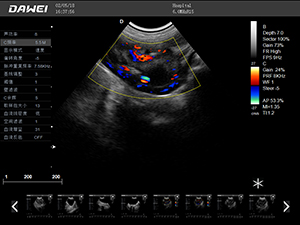

F5-VET彩色多普勒動物超聲診斷儀

F5-VET是一款性能可靠的獸用全數字彩色多普勒超聲診斷系統,基于Windows平臺 配置固態盤快速啟動 穩定可靠,融合了全面豐富的臨床應用,結合優異的人機工程學設計,推動了臨床診斷新趨勢。

·探頭接口:≥4個 可配備凸陣、微凸陣、線陣、相控陣、經直腸等各類獸用專用探頭,并配有犬、貓、馬等動物的專用測量軟件,是一款應用全面的獸用彩超。

·中小動物的肝、膽,脾、腎、膀胱、子宮、妊娠等各組織器官的檢查和病變的診斷